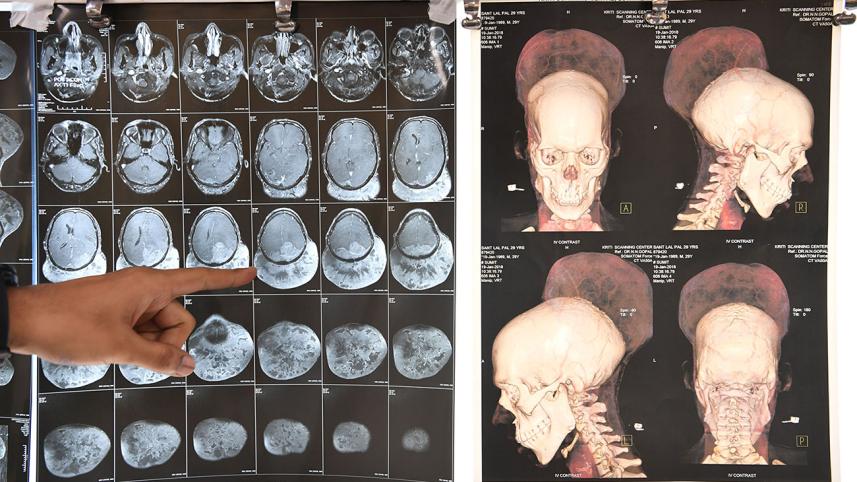

Santlal Pal, a 31-year-old shopkeeper, had been carrying around a tumour weighing nearly two kilos before the surgery on February 14.

Doctors at Mumbai's BYL Nair hospital where he was treated said the tumour was so large that "it appeared as if he had two heads mounted on top of each other".

The tumour weighed 1.87 kilos (four pounds), making it the heaviest ever to be successfully removed from a surviving patient, according to a hospital statement.